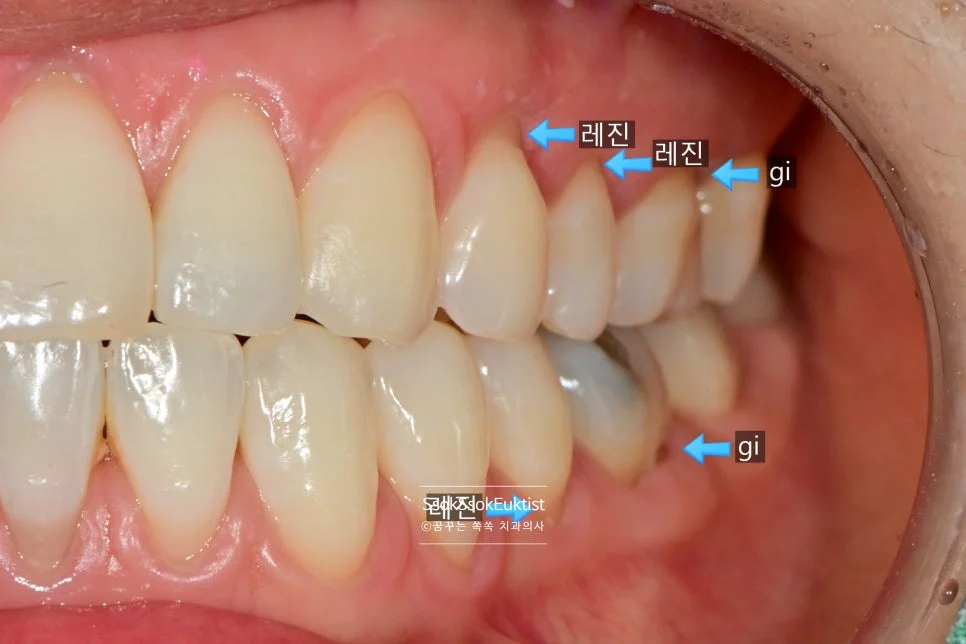

화살표로 표기된 치료 계획 — 앞쪽은 레진, 어금니는 GI

화살표로 표기된 것과 같이 눈에 보이는 앞 쪽 치아는 레진으로, 큰 어금니는 GI로 계획을 세웠는데요.